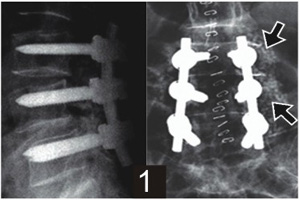

Indications for use:

Product Presentation

|

B-OstIN Granules |

B-OstIN Rod |

B-OstIN Block |